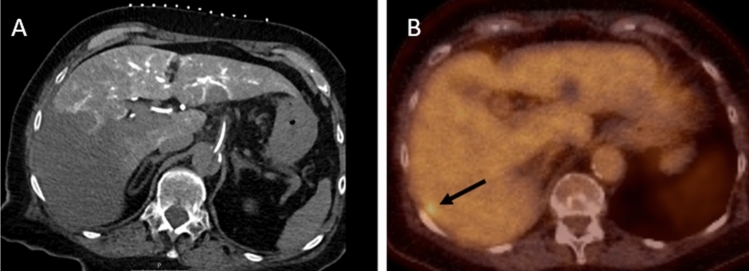

Fig. 5.

Case with aberrant anatomy: aberrant right hepatic artery from the superior mesenteric artery. This case presents a patient with an aberrant right hepatic artery originating from the superior mesenteric artery, resulting in a CTHA (catheter in the common hepatic artery originating from the celiac trunk) of which a large part of the right hepatic lobe could not be assessed. The follow-up 18F-FDG PET-CT reveals a subcapsular CRLM in segment VII that was subsequently invisible on CTHA, due to the segmented vascular supply